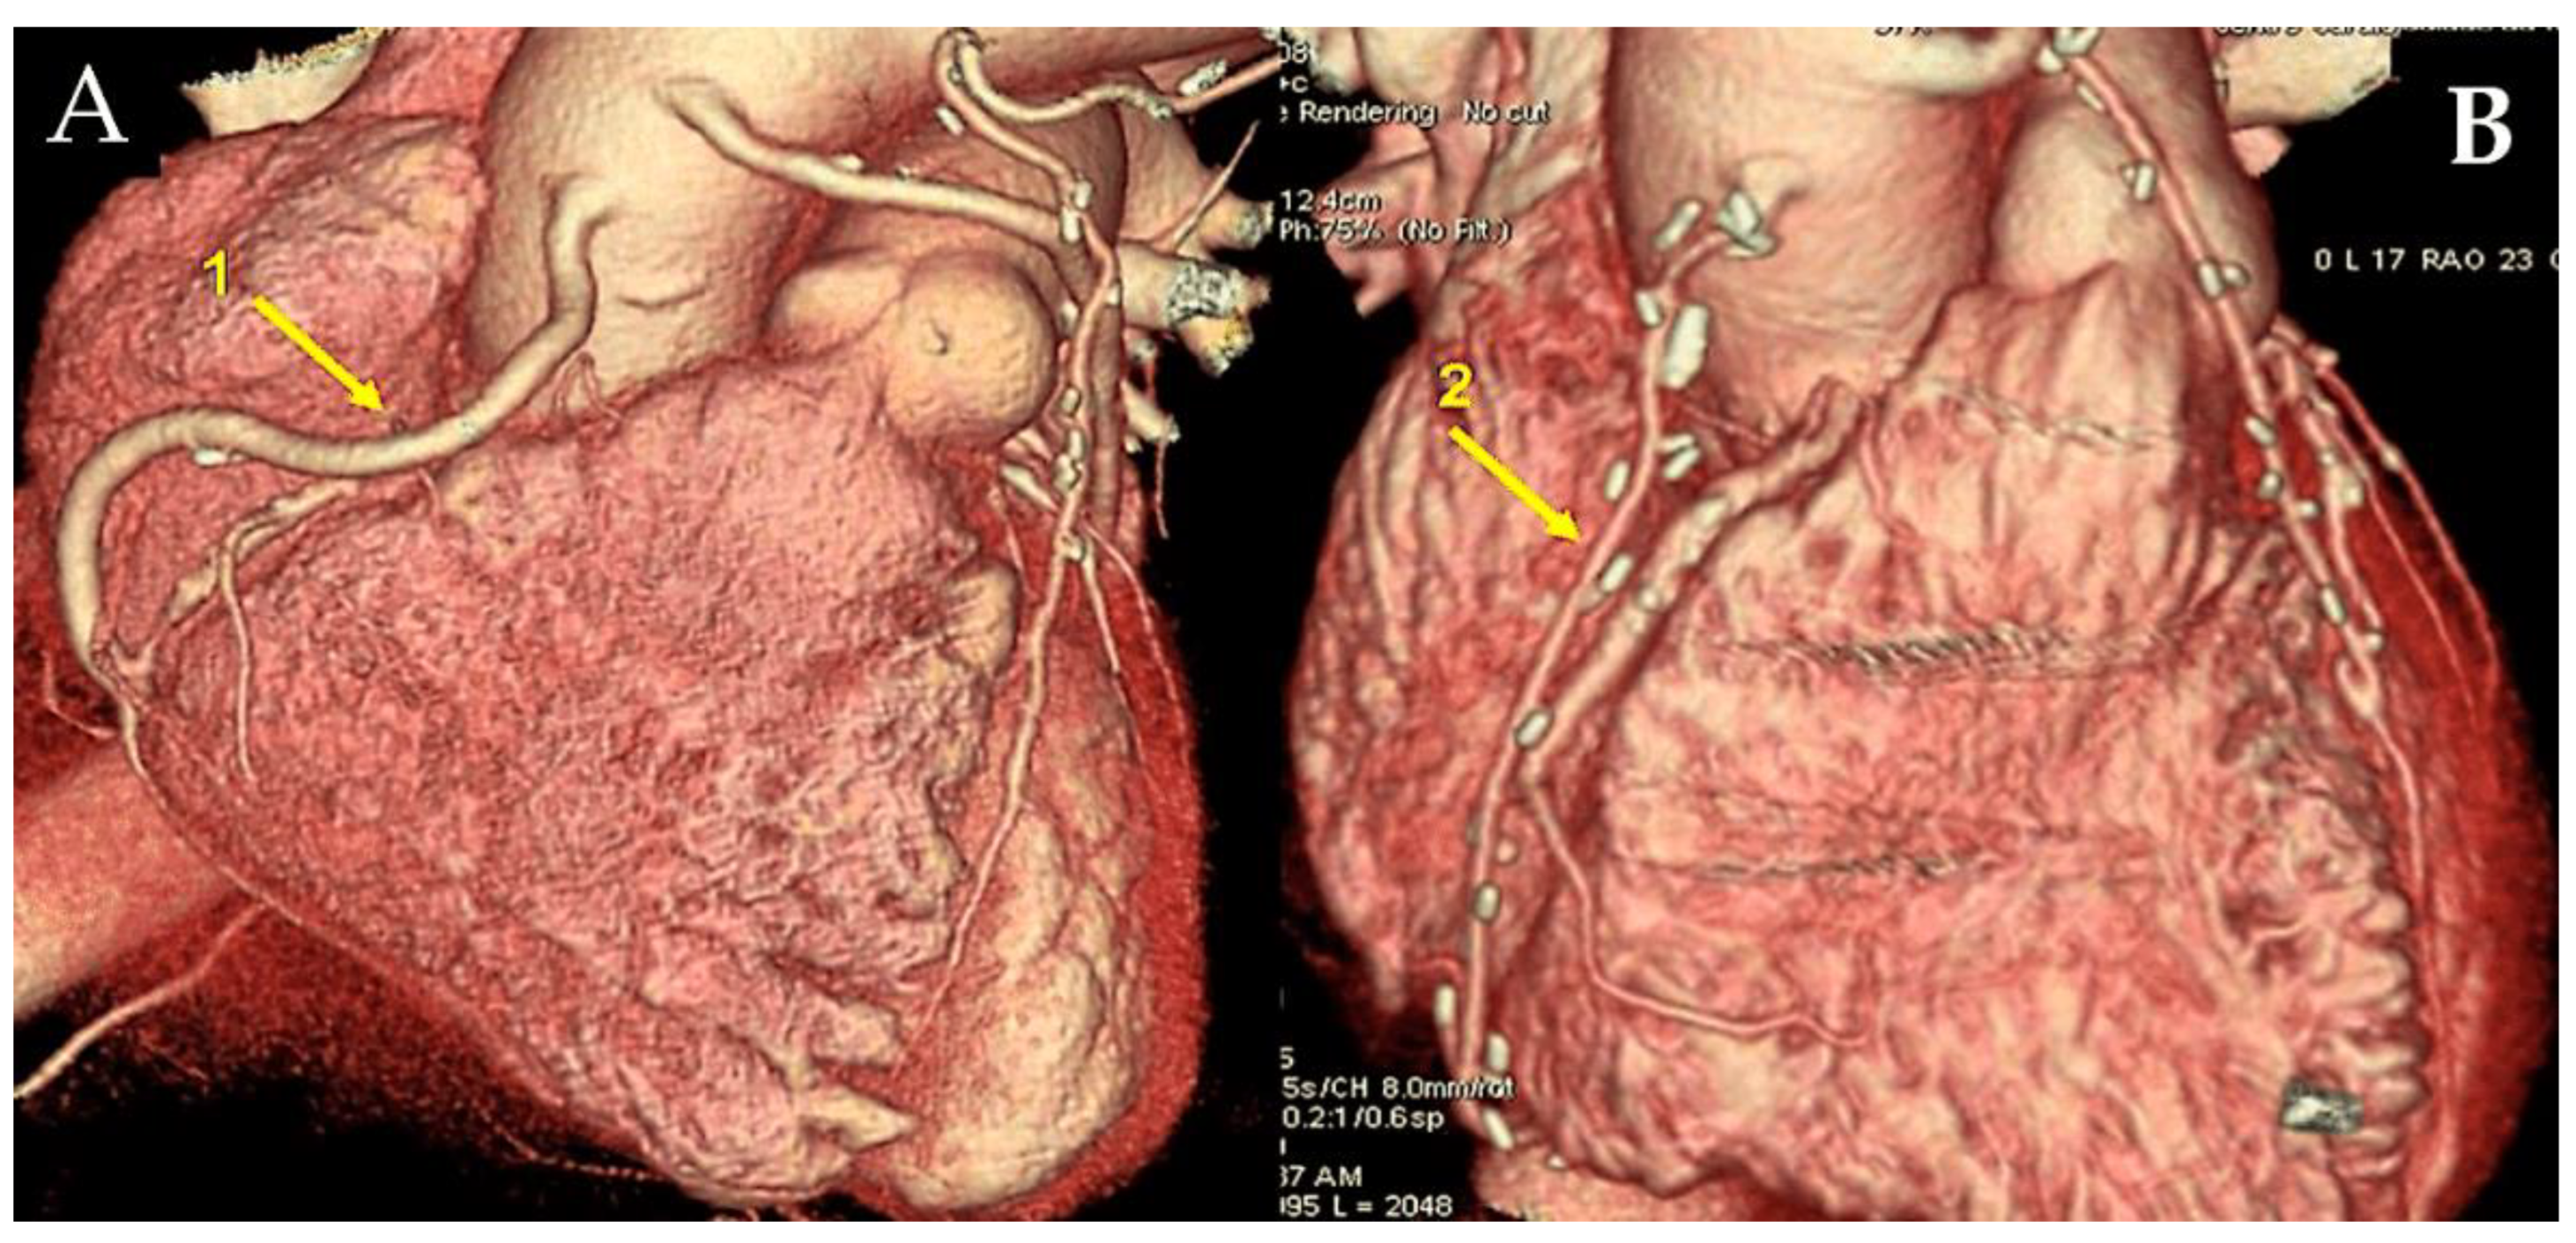

- Di Lazzaro D, Ragni T, Di Manici G, Bardelli G, Da Col U, Grasselli F, Antoniella A, Papa W, Crusco F, Giovagnoni A. Noninvasive midterm follow-up of radial artery bypass grafts with 16-slice computed tomography. Ann Thorac Surg 2006. 82:44-50. [CrossRef]

- Ropers D, Pohle FK, Kuettner A, Pflederer T, Anders K, Daniel WG, Bautz W, Baum U, Achenbach S. Diagnostic accuracy of noninvasive coronary angiography in patients after bypass surgery using 64-slice spiral computed tomography with 330-ms gantry rotation. Circulation. 2006;114:2334-41 . [CrossRef]

- Feuchtner GM, Schachner T, Bonatti J, Friedrich GJ, Soegner P, Klauser A, zur Nedden D. Diagnostic performance of 64-slice computed tomography in evaluation of coronary artery bypass grafts. Am J Roentgenol. 2007; 189:574-80. [CrossRef]